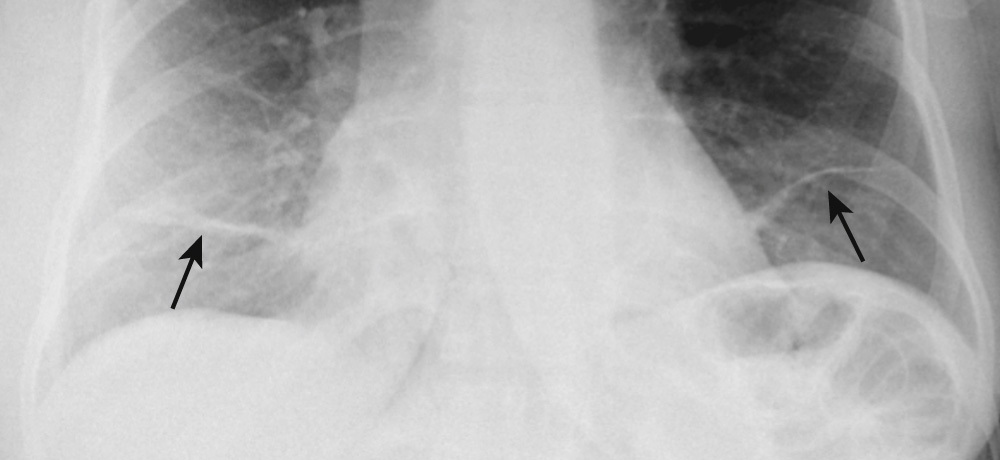

What is going on in this CXR?

These radiographs show atelectasis of the right middle lobe

You can tell that this is atelectasis rather than a consolidation by the downward displacement of the minor fissure

Fissures move towards a collapsed lobe, as do the trachea and heart, and the ipsilateral diaphragm.